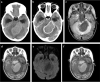

Tuberculosis (TB) remains one of the major public health threats worldwide, despite improved diagnostic and therapeutic methods. Tuberculosis is one of the main causes of infectious disease in the chest and is associated with substantial morbidity and mortality in paediatric populations, particularly in low- and middle-income countries. Due to the difficulty in obtaining microbiological confirmation of pulmonary TB in children, diagnosis often relies on a combination of clinical and radiological findings. The early diagnosis of central nervous system TB is challenging with presumptive diagnosis heavily reliant on imaging. Brain infection can present as a diffuse exudative basal leptomeningitis or as localised disease (tuberculoma, abscess, cerebritis). Spinal TB may present as radiculomyelitis, spinal tuberculoma or abscess or epidural phlegmon. Musculoskeletal manifestation accounts for 10% of extrapulmonary presentations but is easily overlooked with its insidious clinical course and non-specific imaging findings. Common musculoskeletal manifestations of TB include spondylitis, arthritis and osteomyelitis, while tenosynovitis and bursitis are less common. Abdominal TB presents with a triad of pain, fever and weight loss. Abdominal TB may occur in various forms, as tuberculous lymphadenopathy or peritoneal, gastrointestinal or visceral TB. Chest radiographs should be performed, as approximately 15% to 25% of children with abdominal TB have concomitant pulmonary infection. Urogenital TB is rare in children. This article will review the classic radiological findings in childhood TB in each of the major systems in order of clinical prevalence, namely chest, central nervous system, spine, musculoskeletal, abdomen and genitourinary system.